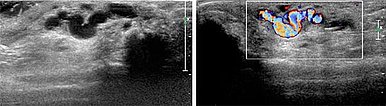

Im Ultraschall imponiert subkutan epifaszial am dritten Finger eine dilatierte Drainagevene aus der digitalen AVM. In der Farbduplexsonographie (FKDS) bestätigt sich der fast-flow arterio-venöse Shunt mit hohem Durchfluss.

Nachdem es technisch nicht möglich ist, die AVM zur Re-Embolisation nur von transarteriell zu behandeln, wird sonographisch gesteuert nun der perkutane Behandlungsweg in Direktpunktionstechnik gewählt.

Perkutanes, sonograhisch gesteuertes Vorschieben der Punktionsnadel in die Drainagevene der digitalen AVM.